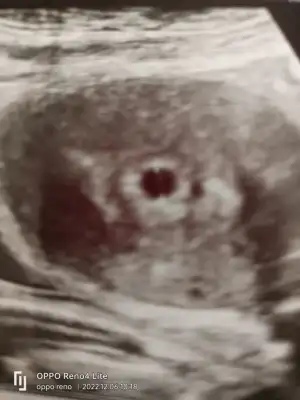

) Bugün beslenme koyamadım oğlum kantinden alın ne istiyorsanız deyip gönderdim valla. Kara kara da düşünüyorum bebek olunca bu tempo nasıl olacak diye